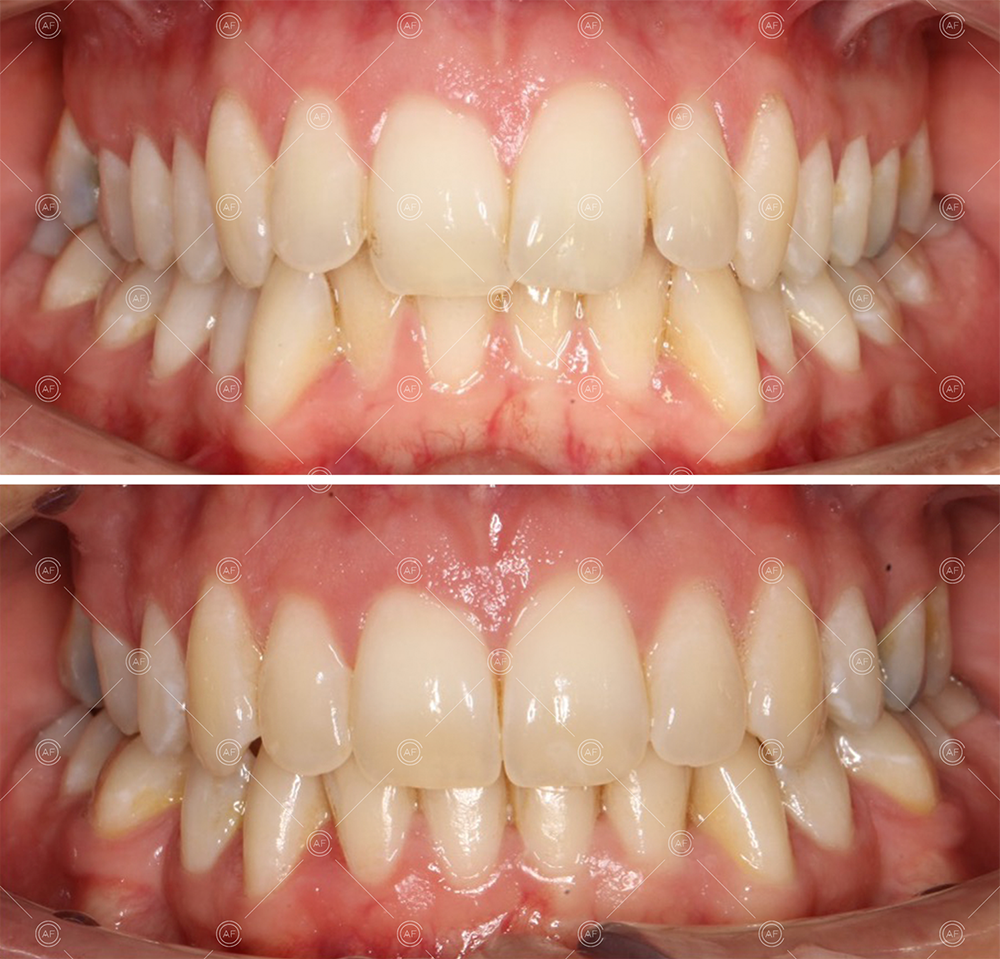

This patient (MH) began her active orthodontic treatment in October 2019 at almost 13 years old. She was unhappy with the appearance of her upper and lower teeth, and especially concerned about the unsightly nature of the high and buccally positioned upper left canine.

about this case…MH presented with class 1 incisors on the class 1 skeletal base with a slightly increased vertical proportion. She had severe crowding in the upper arch and moderate crowding in the lower. Due to the crowding in the lower arch, the lower centre line was off to the left by 2mm.

Buccal segments were essentially class 1 on the right hand side and a full unit class 2 on the left. This is due to buccal exclusion of the upper left 3 and mesial drift of the upper buccal segment.